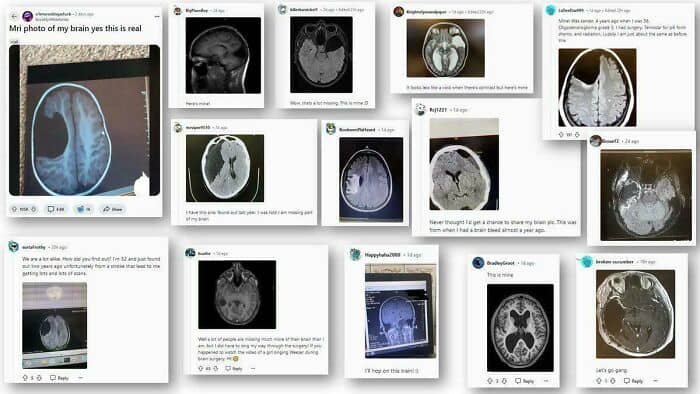

#92 Redditors Are Literally Missing Parts Of Their Brains